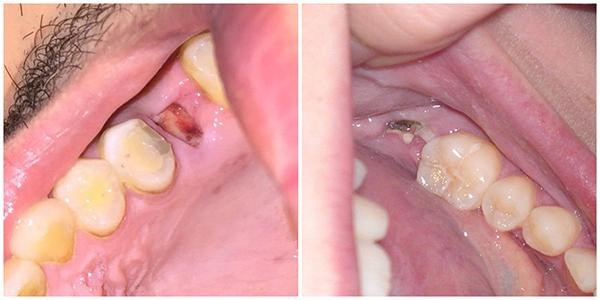

- Viêm huyệt ổ răng: Hiện tượng này thường xảy ra vào ngày thứ 3 sau khi phẫu thuật, bệnh nhân sẽ đối mặt với những cơn đau cơn âm ỉ kèm theo mùi hôi khó chịu từ vị trí mọc răng. Nguyên nhân có thể là cục máu đông không hình thành hoặc hiện tượng thức ăn rơi vào huyệt ổ răng làm nhiễm khuẩn ở vùng răng xung quanh vết mổ.